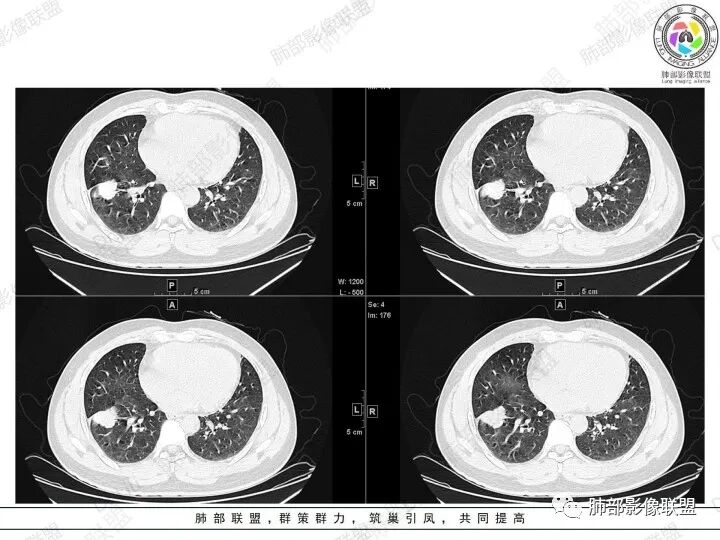

2、胸部CT右肺下叶胸膜下肿块性病变,边缘可见分叶毛刺、边缘膨隆,似有指状凸起,邻近胸膜稍牵拉凹陷,叶间裂以为不明显,提示收缩力较弱。近端支气管进入后截断,病灶内密度尚均匀,增强后可见轻度强化,未见空洞或钙化,并可见血管影进入。右侧肺门及纵隔内可见肿大淋巴结影。无胸腔积液。

3、综合患者临床症状及影像表现,需要考虑肿瘤性病变和非肿瘤性病变,肿瘤性病变需要考虑普通浸润性腺癌或结节型粘液腺癌、淋巴瘤、淋巴上皮瘤样癌、小细胞肺癌等,非肿瘤性病变主要考虑肺脑同病中的隐球菌。①普通浸润性腺癌,以肺外周多年、混合磨玻璃或实性结节/肿块,多见分叶、毛刺、胸膜凹陷、血管集束等征象,本例收缩力较弱、且强化偏轻,不够典型。②粘液腺癌,腺癌的特殊类型。多位于胸膜下(90%位于胸膜下,70%位于下叶胸膜下),边缘清或不清的GGO:提示粘液外渗,少数为纯GGO,缺乏中心纤维化区:毛刺、胸膜凹陷征少,很少胸膜侵犯,淋巴结转移少见,增强后无强化或低强化,本例病灶位于胸膜下,强化轻,收缩力弱,结节期粘液腺癌确实可以符合。③小细胞肺癌,吸烟男性多见,典型征象包括娘小崽大、腊肠样凸起、冰冻纵膈等,本例胸膜下病变大、但肺门淋巴结肿大程度较轻,不符合常见小细胞癌生物学行为,但有可疑指状凸起,小细胞肺癌不能完全除外。④淋巴上皮瘤样癌,少见的恶性肿瘤,患病年龄较轻,肿瘤多位于胸膜下,边缘多光滑,病灶周围可见磨玻璃,毛刺及分叶、胸膜凹陷少见,近端支气管可截断,增强多为中度-明显强化,本例除了强化程度偏轻外,影像表现基本可符合。⑤淋巴瘤,原发肺内淋巴瘤较少见,病灶多位于支气管血管束周围或胸膜下,密度多较均匀,边缘可膨隆也可平直收缩,可见支气管充气征、血管造影征等,强化多为轻中度,本例肺内结节血管穿行自然,局部有血管漂浮,长轴与支气管走行基本一致,肺门淋巴结肿大,不能排除。⑥隐球菌,影像表现可分为孤立结节型、大片实变型、多发结节或实变型、弥漫型。病变多位于胸膜下,边缘平直为主、可伴晕征,可见支气管穿行、部分可见支气管截断,密度多较均匀,部分可伴空洞,增强多为轻中度强化、延迟强化。本例病变位于胸膜下,收缩力弱,强化程度轻,但没有呼吸道症状,病变近端支气管截断,肺门淋巴结大,这些征象都难以用隐球菌解释,基本排除。

结节型粘液腺癌的影像诊断:

1.位于胸膜下(90%位于胸膜下,70%位于下叶胸膜下)

2.边缘清或不清的GGO:提示粘液外渗,少数为纯GGO

3.缺乏中心纤维化区:毛刺、胸膜凹陷征少,很少胸膜侵犯率

4.淋巴结转移少见

5.增强后无强化或低强化